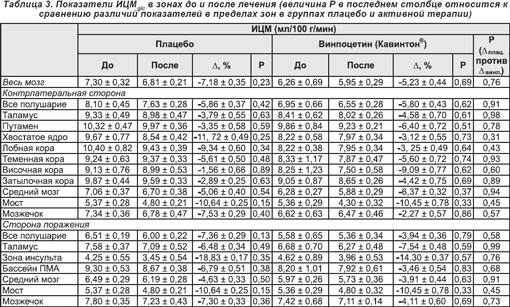

3.2. Исходные уровни и изменения церебрального метаболизма глюкозы

Базальные уровни ИЦМglc для всего мозга (см. таблицу 3) составили 6,96 ± 0,37 во всей группе пациентов и 7,30 ± 0,32 и 6,50 ± 0,73 мг/100 г/мин в подгруппах плацебо и активной терапии соответственно (p = 0,32). После инфузии, в отличие от изменений ЦК, происходило как общее, так и региональное снижение ИЦМglc в обеих подгруппах пациентов. В пораженном полушарии снижение ИЦМglc было более выраженным среди реципиентов плацебо по сравнению с получавшими винпоцетин (Кавинтон®). Данный эффект наблюдался, главным образом, в зоне инсульта (трехсторонний ANOVA-анализ: (F(5,5) = 0,39; p < 0,85); двуточечные t-критерии приведены в таблице 3).